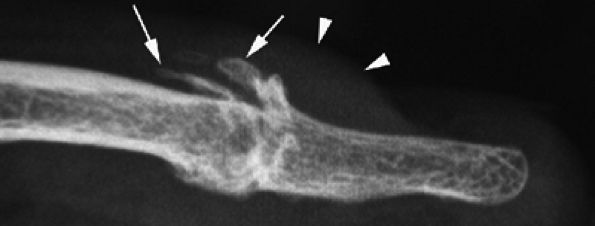

![]() |

|

FIGURE 11.114 ● Mucoid pseudocyst. Lateral view radiograph showing distal interphalangeal joint osteoarthritis with dorsal osteophytes (arrows) and thickening of the posterior nail fold (arrowheads).